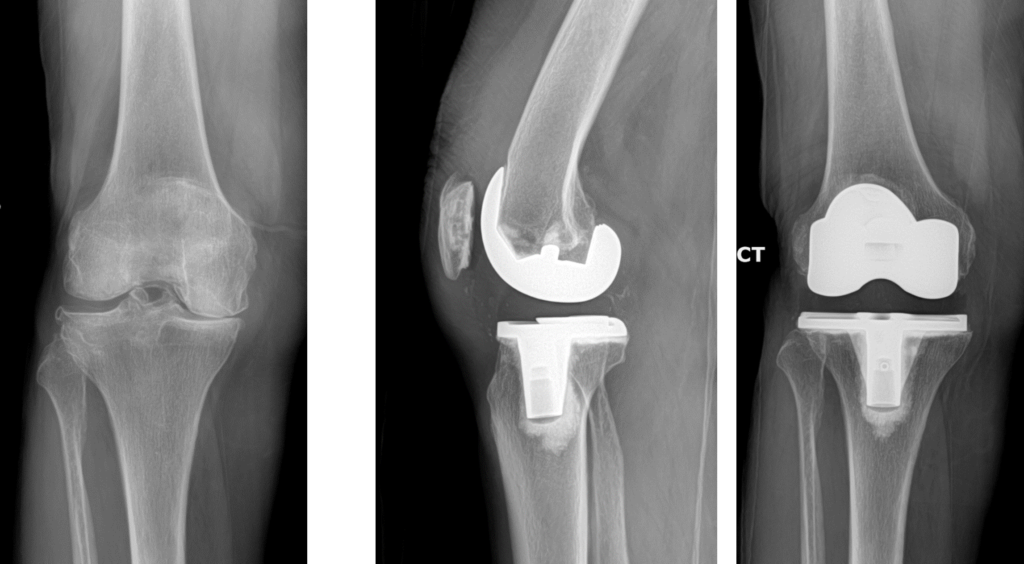

Bone surfaces at joints (such as the hip, knee, or shoulder) are covered by a smooth tissue called cartilage which allows the surfaces to move against each other while providing protection to the bone ends. Arthritis (also called degenerative joint disease) is a condition where this cartilage wears away and changes begin taking place within the joint (figure 1). As cartilage degeneration occurs, pain can develop which can be severe and functional limitations can result.

Knee replacement is a surgery whereby the surfaces of the knee joint are replaced by artificial surfaces (commonly metal and plastic parts). The arthritic surfaces of the femur (thigh bone) and tibia (shin bone) at the knee are removed and replaced with metal load bearing surfaces. A plastic liner that will fit onto the new metal tibial surface and articulate with the new artificial metal surface on the femur is inserted as well (figure 2). A plastic (or metal and plastic) piece may or may not be used to resurface the patella (knee cap) depending upon how much arthritis is present in this part of the joint.